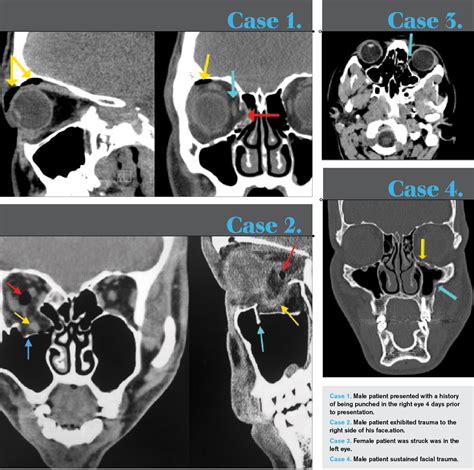

To accurately diagnose an orbital floor fracture, healthcare providers rely on a combination of physical examination and advanced imaging. During the physical exam, a surgeon will test the range of motion of your eyes and check for nerve sensation in the face. To confirm the diagnosis, the gold standard is a Computed Tomography (CT) scan of the orbits.

CT Scan (Coronal View) Best visualization of the orbital floor and sinus involvement.